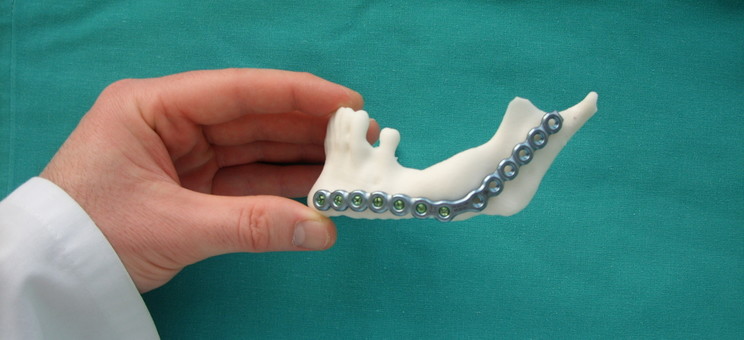

Dr inż. Paweł Turek z Katedry Technik Wytwarzania i Automatyzacji Politechniki Rzeszowskiej stworzył model żuchwy wykonany techniką druku 3D. Taki wydrukowany, medyczny model żuchwy może pomóc chirurgowi dopasować wszczepiany implant do konkretnego pacjenta, ale jeszcze przed zabiegiem.

- Dzięki zastosowaniu modeli żuchwy wykonanych przy użyciu druku 3D, znacznie skrócono czas przeprowadzenia zabiegu chirurgicznego, a także zminimalizowano wystąpienie komplikacji śródoperacyjnych - wyjaśnia twórca modelu dr inż. Paweł Turek, adiunkt w Katedrze Technik Wytwarzania i Automatyzacji PRz. - Dodatkowo opracowano procedurę umożliwiającą komputerowe (wirtualne) odtworzenie geometrii żuchwy sprzed wystąpienia urazu.

Kolejnym etapem prac badawczych jest nawiązanie współpracy między Politechniką Rzeszowską, Uniwersytetem Rzeszowskim, podkarpackimi szpitalami oraz przedsiębiorstwami branży medycznej i technologii medycznej w ramach Stowarzyszenia Klastra „Technologia w Medycynie” – TECHNOMED. To w ramach działalności klastra, wykonywane są obecnie modele oraz szablony chirurgiczne technikami druku 3D (m.in. miednicy, kości udowej), które w znaczący sposób ułatwiają zaplanowanie oraz przeprowadzenie zabiegu przez chirurgów. Planowane jest dalsze rozszerzenie badań w ramach działalności klastra.